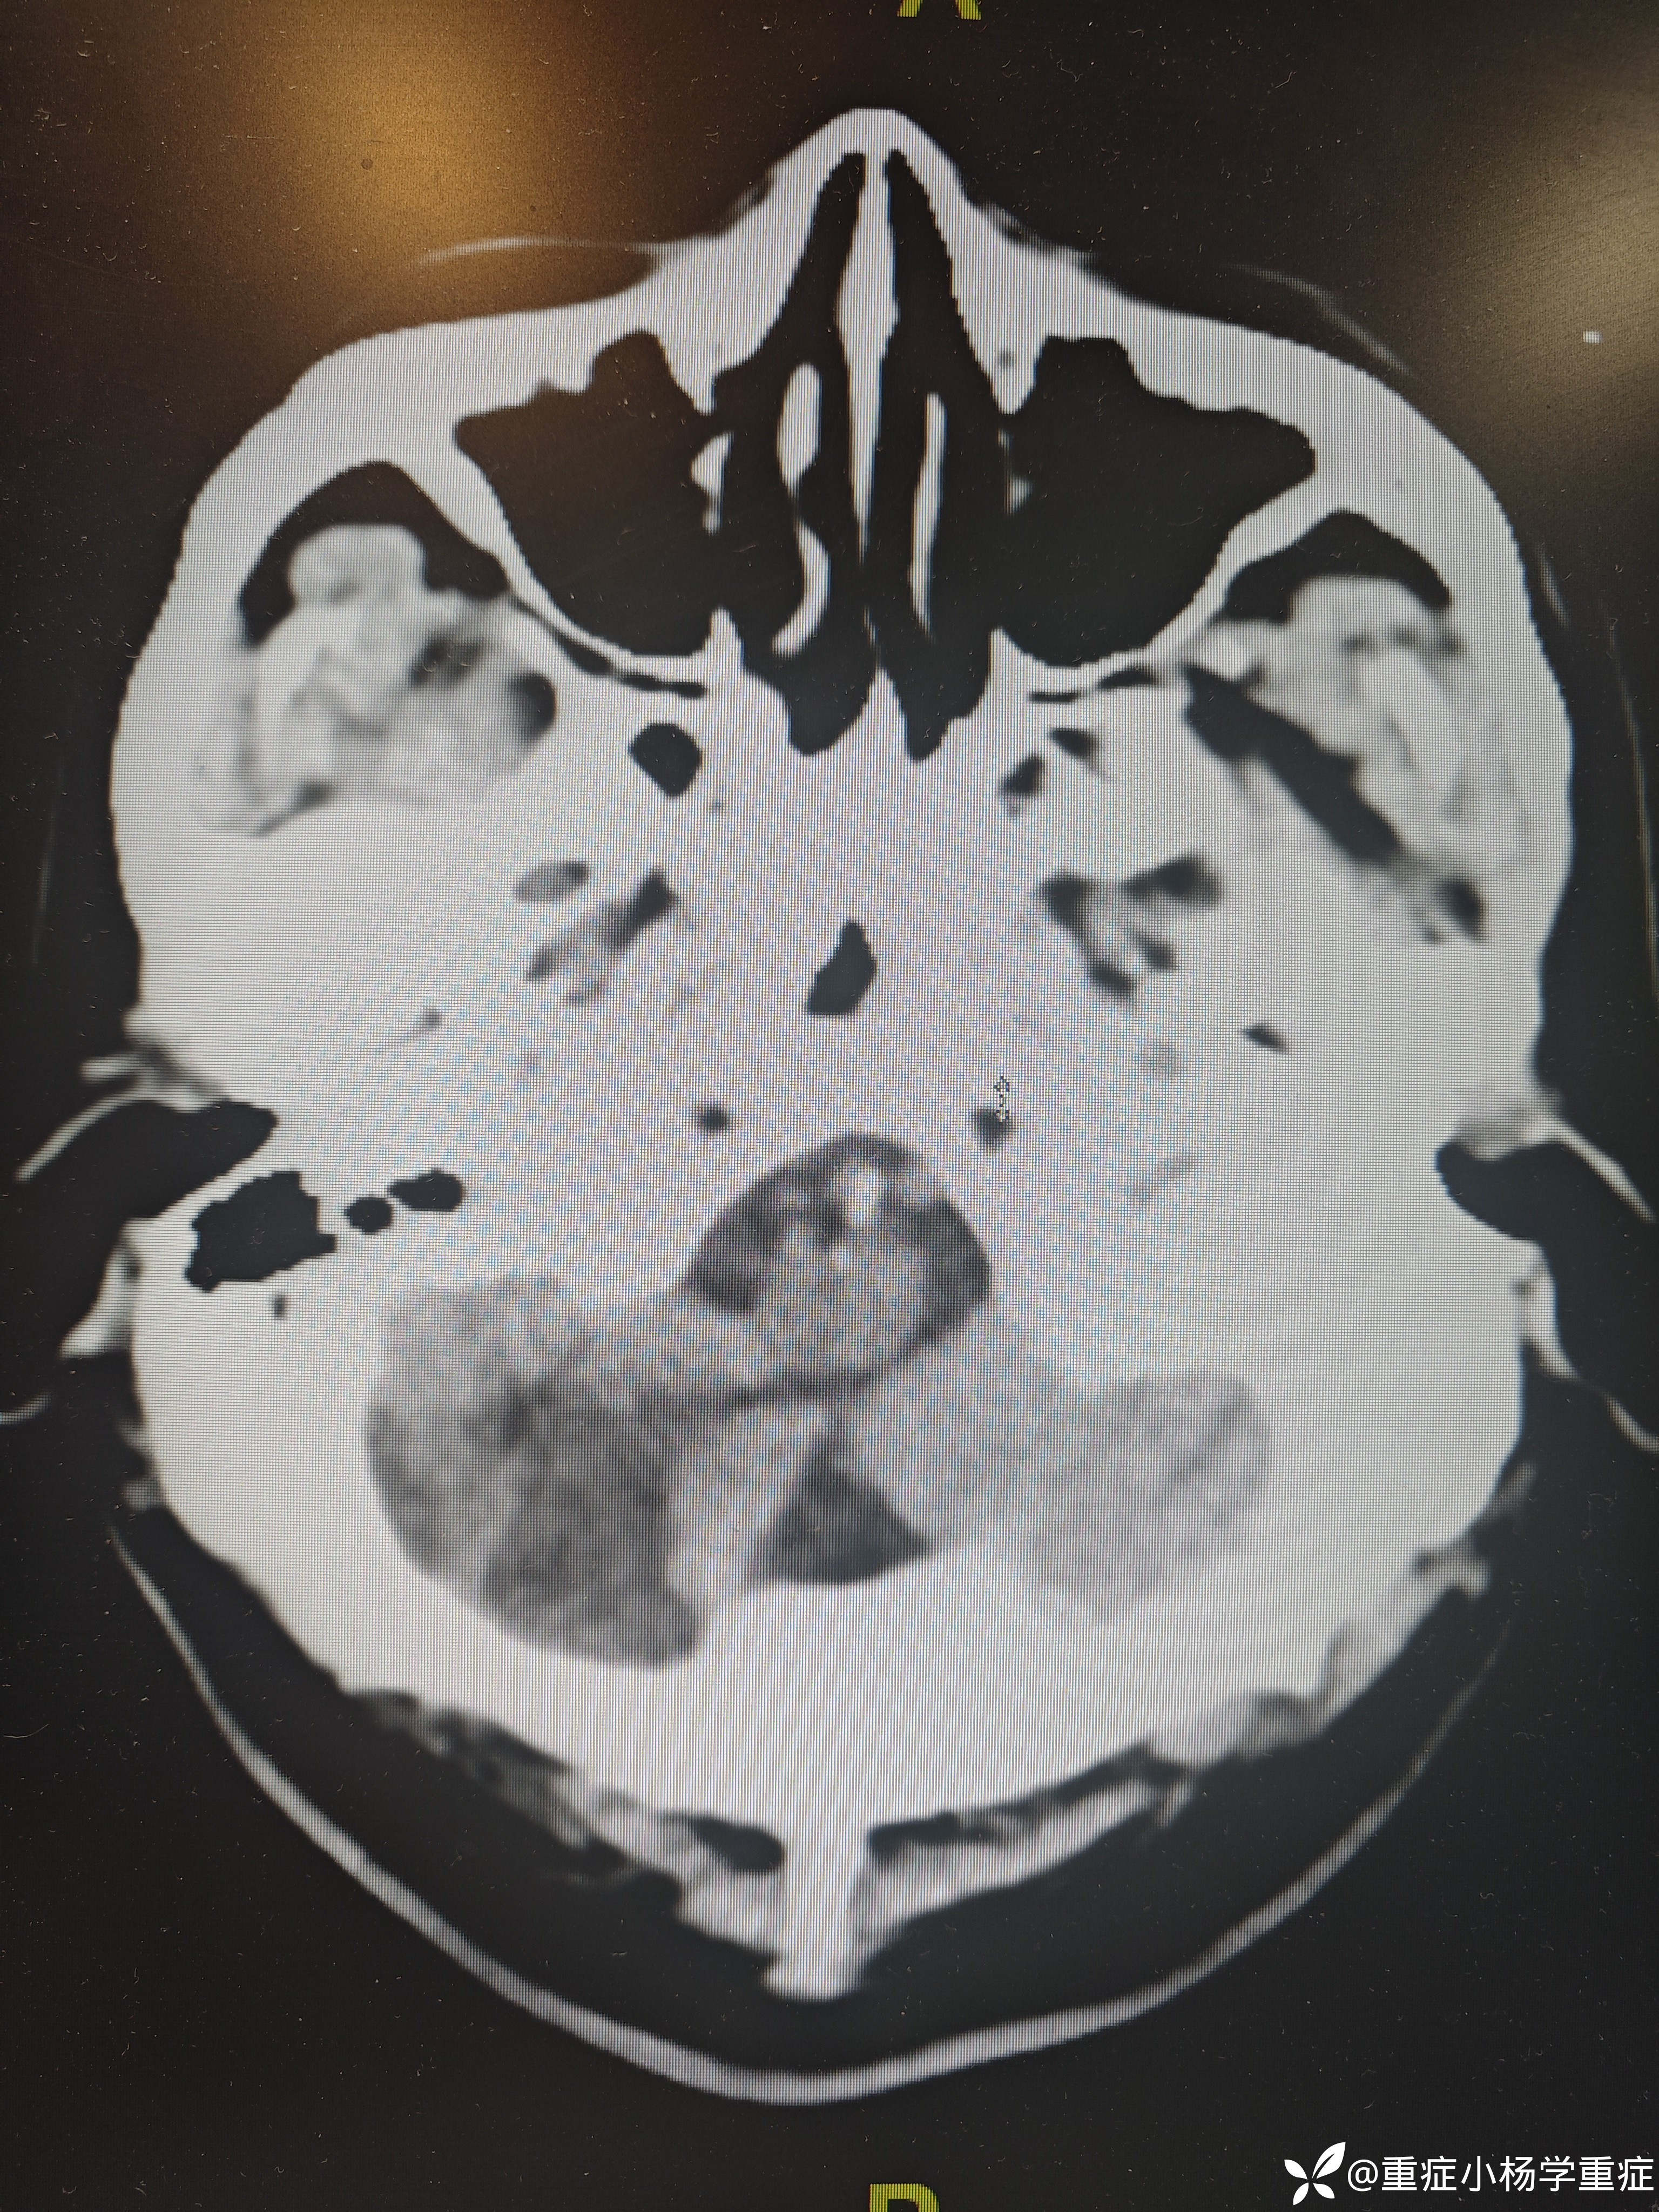

飞跃迷雾1 达人已点赞因“代:脑出血术后2月余,痰多伴呼吸困难1小时”入院。因头痛至医院检查ct提示蛛网膜下腔出血,后完善CTA提示脑血管畸形,至省内医院行介入栓塞后出现脑梗塞,考虑压迫延髓导致呼吸功能损伤,术后第二天予以气切,后出现四肢瘫痪,近期ct如下